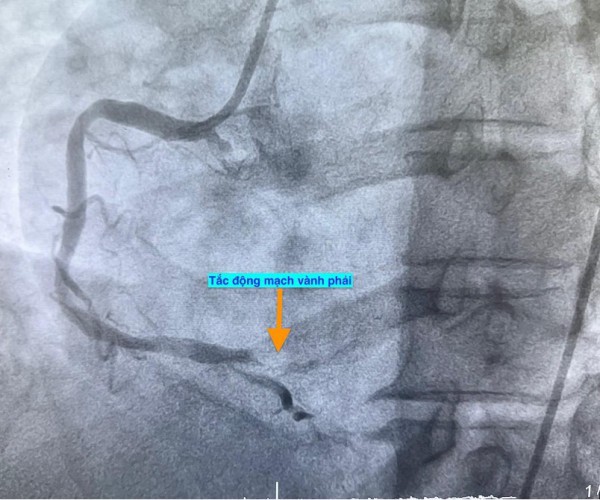

Trường hợp thứ hai, lúc 9 giờ 5 phút, nam bệnh nhân 53 tuổi nhập viện vì chóng mặt và nóng rát thượng vị. Điện tâm đồ ghi nhận nhồi máu cơ tim cấp vùng dưới. Kết quả chụp mạch vành xác định bệnh nhân cũng bị tắc động mạch vành phải.

Hình ảnh chụp mạch vành cho thấy các bệnh nhân bị tắc mạch máu tim (do mảng xơ vữa, huyết khối) dẫn đến tình trạng thiếu máu cục bộ và nhồi máu cơ tim cấp